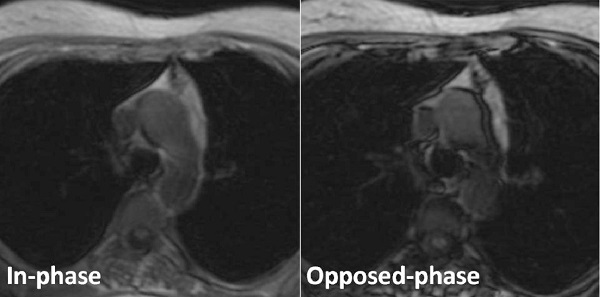

CTやMRIにおいて、①腫瘤内部に脂肪成分を含むため、まだら状の小結節性低吸収域が見られる、②MR脂肪抑制像(化学シフトMRイメージング)で正常胸腺と同じ生理的な脂肪成分が存在すれば胸腺過形成(Radiology2007;243:869-76)。

脂肪成分を含まない胸腺腫や胸腺癌(悪性胸腺腫、浸潤性胸腺腫)と鑑別されます。